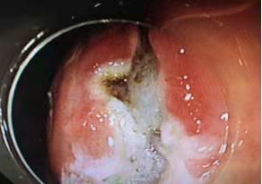

消化内科内镜中心目前是渭南市占地面积配套设施最齐全的内镜中心,达到了省级先进水平,能够满足各种胃肠检查治疗技术。每年进行胃肠镜检查15000余例,各种治疗2千余例,进行常规胃肠镜下治疗外可以进行 食道异物取出、食道及结肠狭窄扩张及支架置入、食道静脉曲张套扎、胃底静脉硬化剂注射、胃底曲张静脉组织胶注射、胆道ERCP检查,胆道支架,胆道结石取出、超声内镜检查(EUS)、胃肠粘膜下病变剥离术(ESD)等,其中 “三E”技术均达到了省内先进技术,填补了渭南地区在心血管领域的多项空白。急诊内镜下治疗上消化道出血达到了省内先进水平。科室重视科研,目前有两项独立完成的市级科技新项目,同时与省级单位联合两项省级课题,近3年完成省级以上论文40篇,其中两篇SCI文章。科室是渭南市消化内镜质控中心、渭南市消化内科专业委员会主委单位、渭南市消化内镜专业委员会主委单位、担负渭南地区消化及消化内镜专业学术的发展。